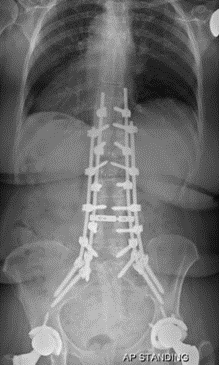

图5 脊柱远端融合节段越多,如包括L5-S1水平固定到骶骨或髂骨,发生交界性后凸的可能性越大

图24 左:长节段固定至髂骨;右:长节段固定